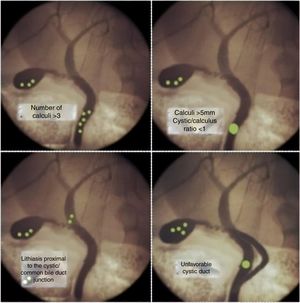

When inflammation alters the normal anatomy of Calot’s triangle, or rare conditions occur associated with the choledocholithiasis, resolution can be difficult. Unfavorable situations may be related to the size, number and location of the stones or anatomical variables of the biliary tree2–4 (Fig. 1).

Enlargement of cysticotomy over a calculusWhen the cystic duct/calculus ratio is <1 (meaning that the diameter of the cystic duct is smaller than the choledochal calculus), the potential success of transcystic instrumentation is drastically lower.4

The maneuver we use involves snaring the stone with the basket, dragging it to the cystic duct, and expanding the cysticotomy over the stone (Fig. 2C).

New dissection of the cystic ductAdequate dissection of the cystic duct provides a critical view of safety. However, in unfavorable cystic ducts (twisted or presenting cystic duct stones7,8), it is difficult to perform intraoperative cholangiography, and even more so transcystic instrumentation.

Angular cysticotomy or minimal choledochotomyThe presence of intrahepatic stones is uncommon, and even more so is the impossibility of descending them beyond the cystic-choledochal junction. When faced with this exceptional situation, we perform a new cysticotomy on the lower side, close to the junction, which allows us to direct the basket snare towards the intrahepatic bile duct.9